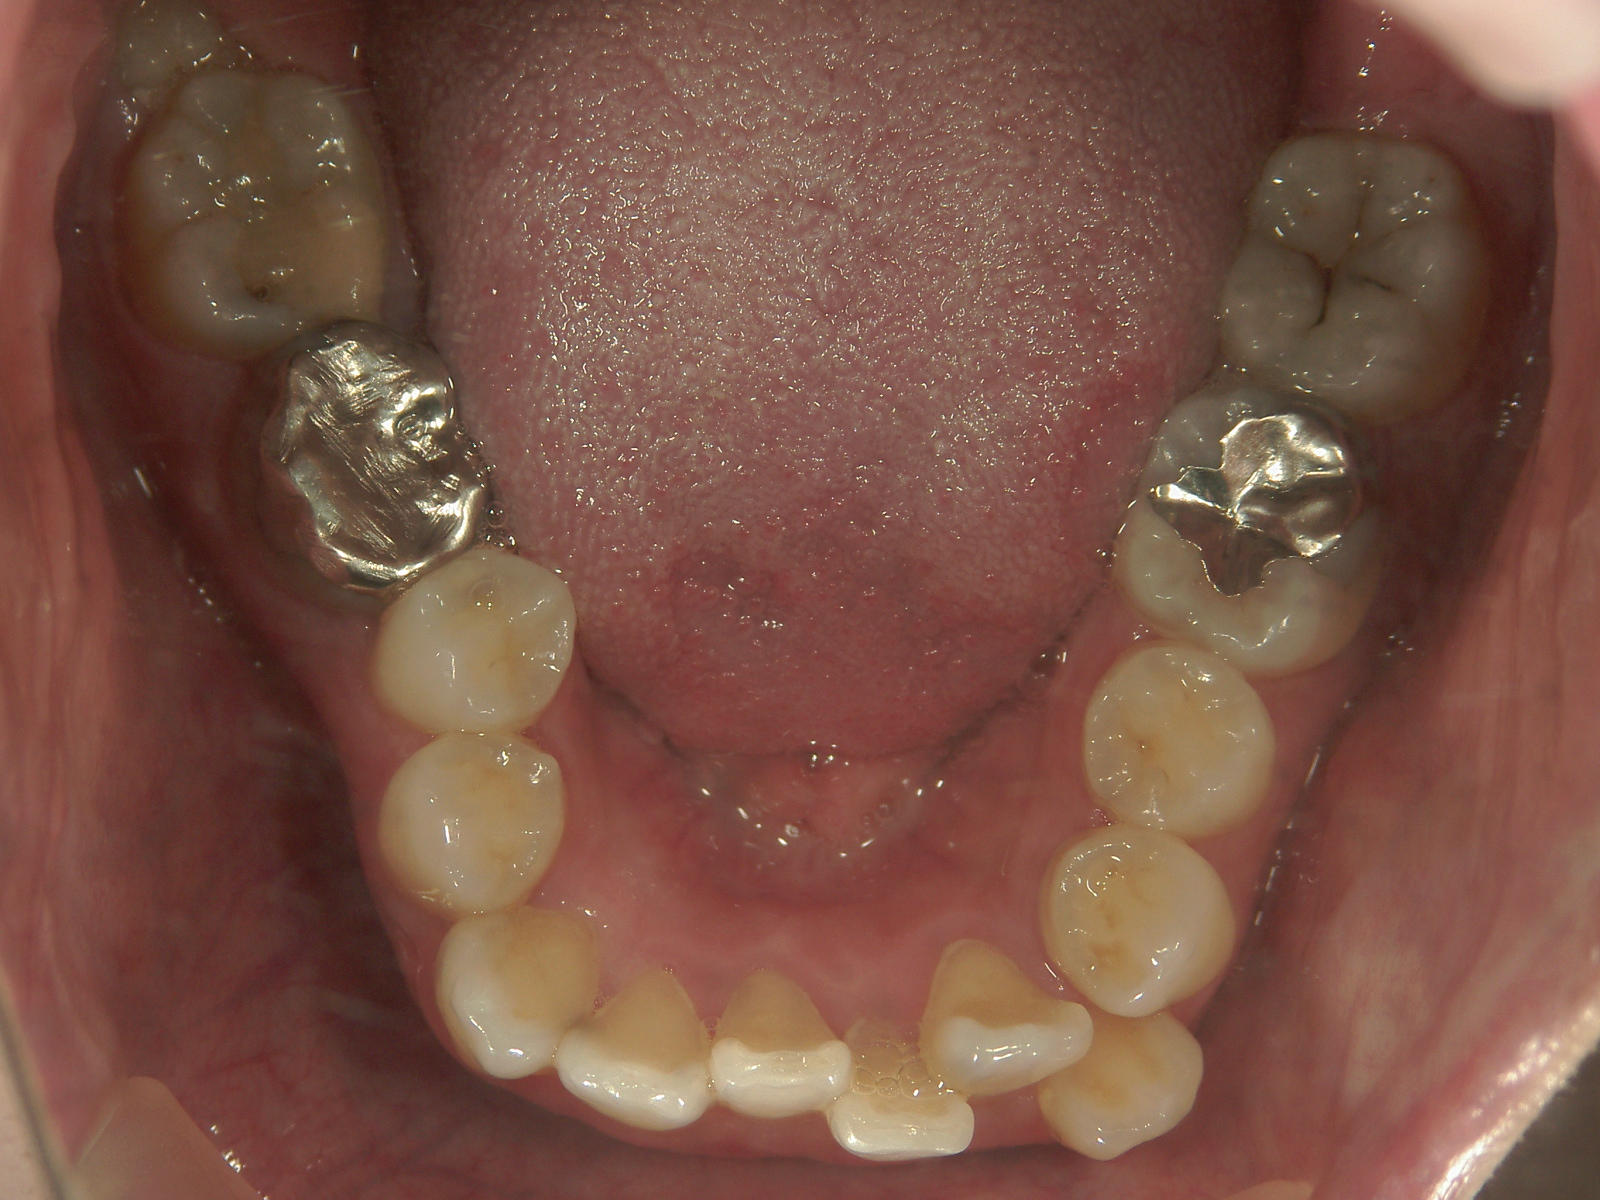

左右上 第一小臼歯(2本)、左右下 第二小臼歯(2本)を抜歯。

矯正装置(BH・QH)を併用。

ミニインプラント、アップライトスプリングを併用。

右下大臼歯(2本)をZ冠、E-MAX(On)に変更。